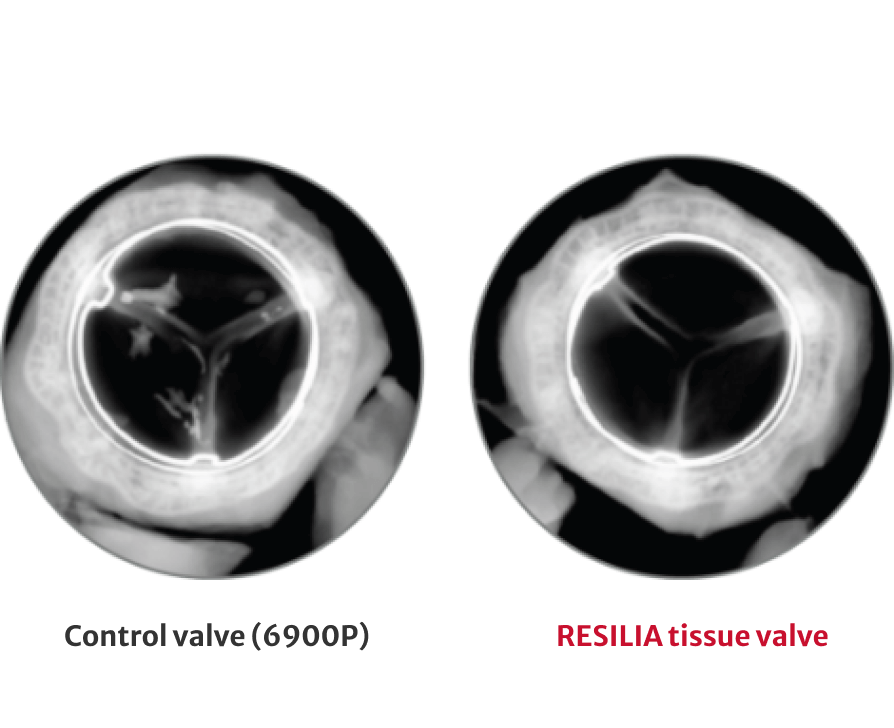

RESILIA tissue* builds on the trusted ThermaFix process and is treated with a novel preservation technology to resist calcification more effectively and allow for dry storage.1

Stable-capping permanently blocks free aldehydes to prevent calcium binding within the tissue

Mitigates calcium-attracting glutaraldehyde residuals and enables dry tissue storage for increased ease of use

72% less calcium content after 8 months